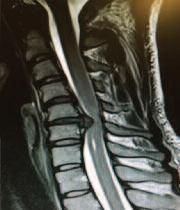

Ηαγκυλοποιητική

σπονδυλίτιδα (Α Σ ), είναι

μια χρόνια φλεγμονώδης

νόσος, η οποία προσβάλλει

νέους ενήλικες και συνήθως

ξεκινάει πριν την ηλικία των 45 ετών.

Οι ασθενείς παρουσιάζουν πόνο και δυσκαμψία κυρίως στην μέση τους αλλά

μπορεί να προσβληθούν και οι υπόλοιπες μοίρες της σπονδυλικής

στήλης, όπως η πλάτη και ο αυχένας.

Διάγνωση

Η διάγνωση της Α.Σ. γίνεται κυρίως

κλινικά, δηλαδή με τον τον τυπικό πόνο

στη σπονδυλική στήλη, ο οποίος επιδεινώνεται με την ακινησία. Εκτός από τις μυοσκελετικές εκδηλώσεις, η νόσος μπορεί να προσβάλει τους οφθαλμούς και να προκαλέσει ραγοειδίτιδα

Επίσης, σε πολλούς ασθενείς μπορεί να υπάρχει ψωρίαση στο ιστορικό τους ή να πάσχουν από κάποια φλεγμονώδη πάθηση του εντέρου (νόσος Crohn ή ελκώδη κολίτιδα)

Από τις εργαστηριακές εξετάσεις ενίοτε βρίσκονται αυξημένοι οι δείκτες φλεμονής(ΤΚΕ,CRP)

Σε αρκετούς ασθενείς ανιχνεύεται το

αντιγόνο HLA - B27 ,το οποίο υποβοηθεί την διάγνωση Μεγάλη βοήθεια στη διάγνωση προσφέρουν οι ακτινογραφίες κυρίως των ιερολαγονίων αρθρώσεων, των οποίων η προσβολή είναι παθογνωμονική της νόσου Συνήθως οι ιερολαγόνιες προσβάλλονται εξαρχής κάτι όμως που δεν φαίνεται πάντα στην απλή

ακτινογραφία και απαιτείται μαγνητική τομογραφία ιερολαγονίων αρθρώσεων Αυτή μπορεί να δείξει χαρακτηριστικές βλάβες της νόσου, όπως οστικό οίδημα, διαβρώσεις κ α